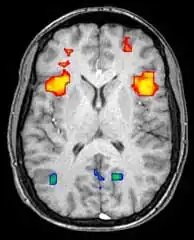

Функциональная магнитно-резонансная томография (фМРТ) основана на парамагнитных свойствах оксигенированого и дезоксигенированого гемоглобина и дает возможность увидеть изменения кровообращения головного мозга в зависимости от его активности. Такие изображения показывают, какие участки мозга активированы (и каким образом) при исполнении определённых заданий.

Большинство фМРТ-томографов дают возможность представлять исследуемому разные визуальные изображения, звуковые и тактильные стимулы и производить действия типа нажатия кнопки или движения джойстиком. Следовательно, фМРТ можно использовать, чтобы показывать структуры мозга и процессы, связанные с восприятием, мышлением и движениями. Разрешение фМРТ на данный момент 2—3 мм, ограниченное кровоснабжением, влияющим на нейрональную активность. Она существенно заменяет ПЭТ при исследовании типов активации головного мозга. ПЭТ, однако, одерживает значительное преимущество, будучи в состоянии идентифицировать специфические клеточные рецепторы или (моноаминовые трансмиттеры) связанные с нейромедиаторами, благодаря визуализации меченных радиоактивно рецепторных «лигандов» (рецепторный лиганд — химическое вещество, связанное с рецептором).

фМРТ используют как для медицинских исследований, так и (всё шире) в диагностических целях. Так как фМРТ исключительно чувствительна к изменениям кровообращения, она очень хорошо диагностирует ишемию, как например при инсульте. Ранняя диагностика инсультов всё важнее в неврологии, так как медикаменты, растворяющие свернувшиеся сгустки крови, можно использовать в первые несколько часов и при определённом типе инсульта, в то время как они могут быть опасными при дальнейшем использовании. фМРТ в таких случаях дает возможность принять правильное решение.

фМРТ можно использовать также для распознавания мыслей. В эксперименте с точностью 72 %—90 %[5] фМРТ смогла установить, какой набор картинок смотрит испытуемый[6]. Скоро, по мнению авторов исследований, благодаря этой технологии можно будет установить, что именно видит перед собой испытуемый[6]. Эту технологию можно будет использовать для визуализации снов, раннего предупреждения болезней головного мозга, создания интерфейсов для парализованных людей для общения с окружающим миром, маркетинговые рекламные программы и борьба с терроризмом и преступностью[6].